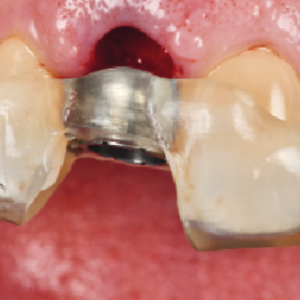

La estabilidad del hueso marginal y del tejido blando alrededor de los implantes dentales se ha establecido como la principal característica para asegurar la salud del implante.La condición...

La integración del tejido blando periimplantario sigue siendo fundamental para el éxito a largo plazo de la terapia con implantes. La formación de una barrera temprana y duradera para proteger las...